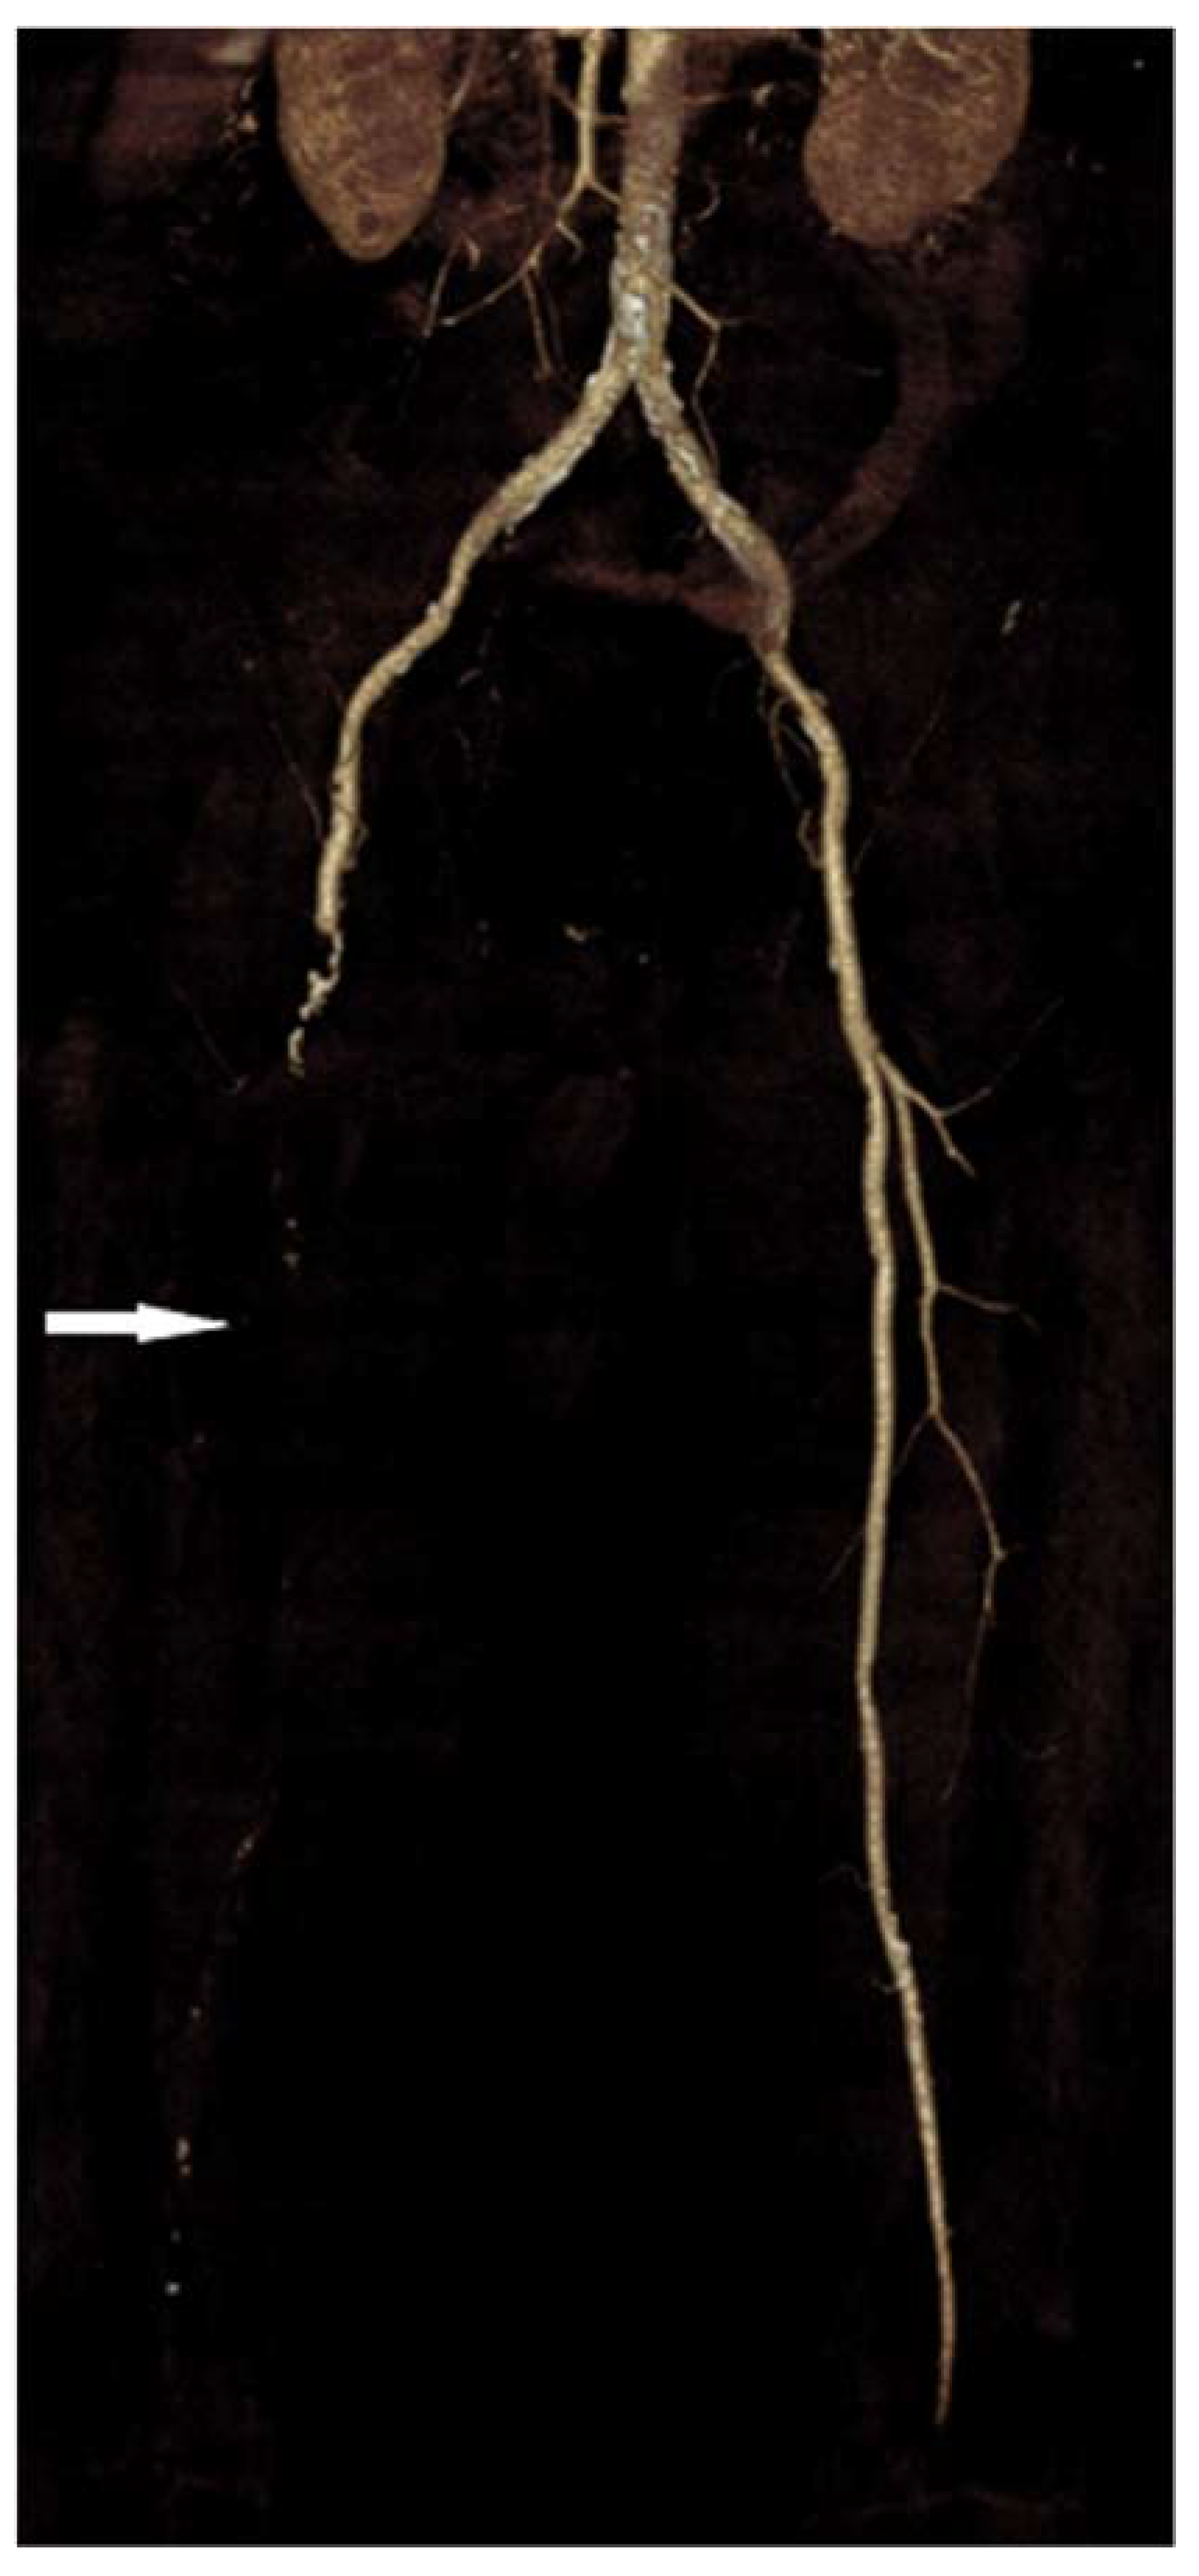

| Patients with unilateral occlusions, n (%) | 1 (5.9) | 1 (5.9) | 0 |

| Patients with bilateral occlusions, n (%) | 16 (94.1) | 12 (70.6) | 4 (23.5) |

| Occlusions by stenosis degree, n (%) | |||

| Subocclusions | 126 (62.1) | 100 (49.3) | 26 (12.8) |

| Total occlusions (100%) | 77 (37.9) | 59 (29.1) | 18 (8.8) |

| Thrombus length, n (%) b | |||

| Short segment occlusions (<10 cm) | 36 (32.4) | 34 (30.6) | 2 (1.8) |

| Intermediate segment occlusions (10–20 cm) | 21 (18.9) | 13 (11.7) | 8 (7.2) |

| Long segment occlusions (>20 cm) | 54 (48.7) | 39 (35.1) | 15 (13.5) |